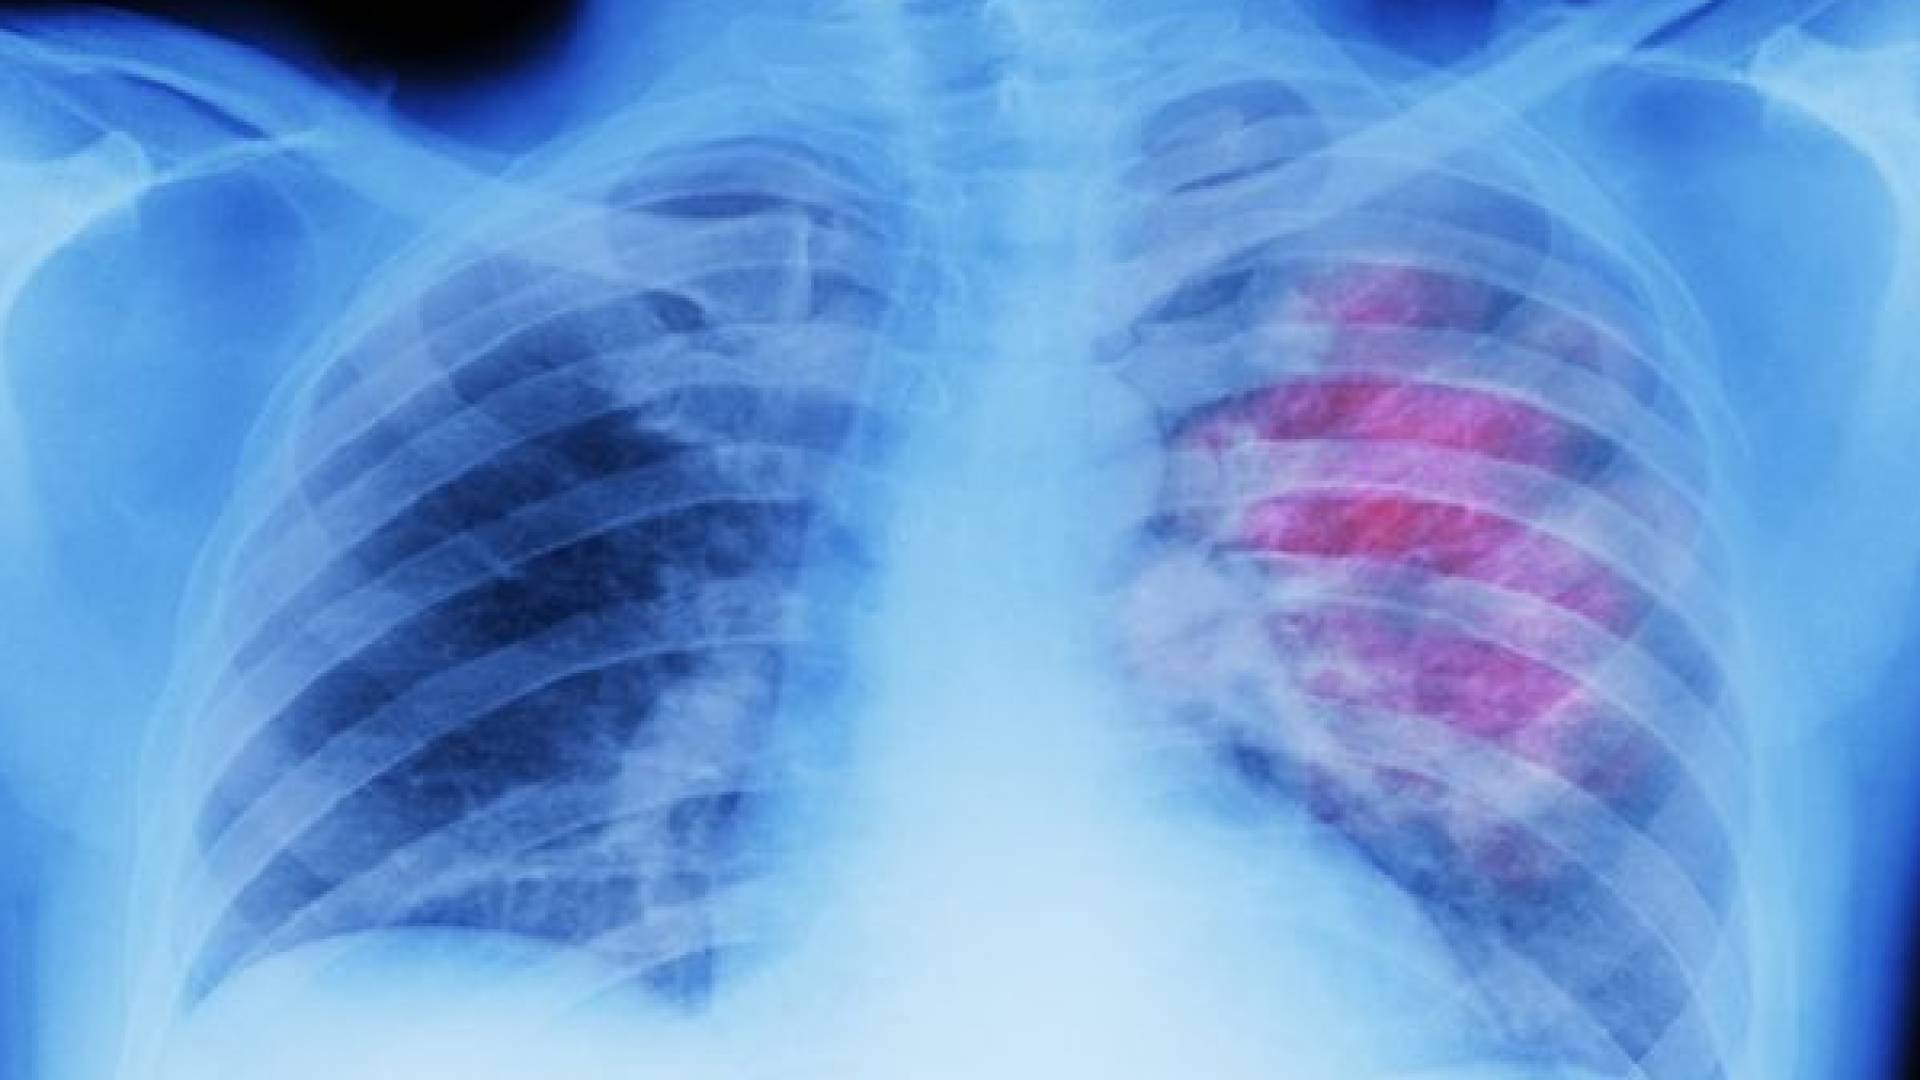

وأوضح قائلا: "الضرر الأكبر يكمن في إمكانية حدوث الوذمة الرئوية (الاستسقاء الرئوي)، حيث تتجمع السوائل بكثافة في الرئتين. هذا التجمع يمنع تبادل الأكسجين بشكل فعال".

وحذر من أن هذه الحالة قد تؤدي إلى "تدمير جزئي أو كلي للقصبات الهوائية والأسناخ"، الأمر الذي "يضع المصاب في خطر الفشل التنفسي ويهدد حياته على الفور".